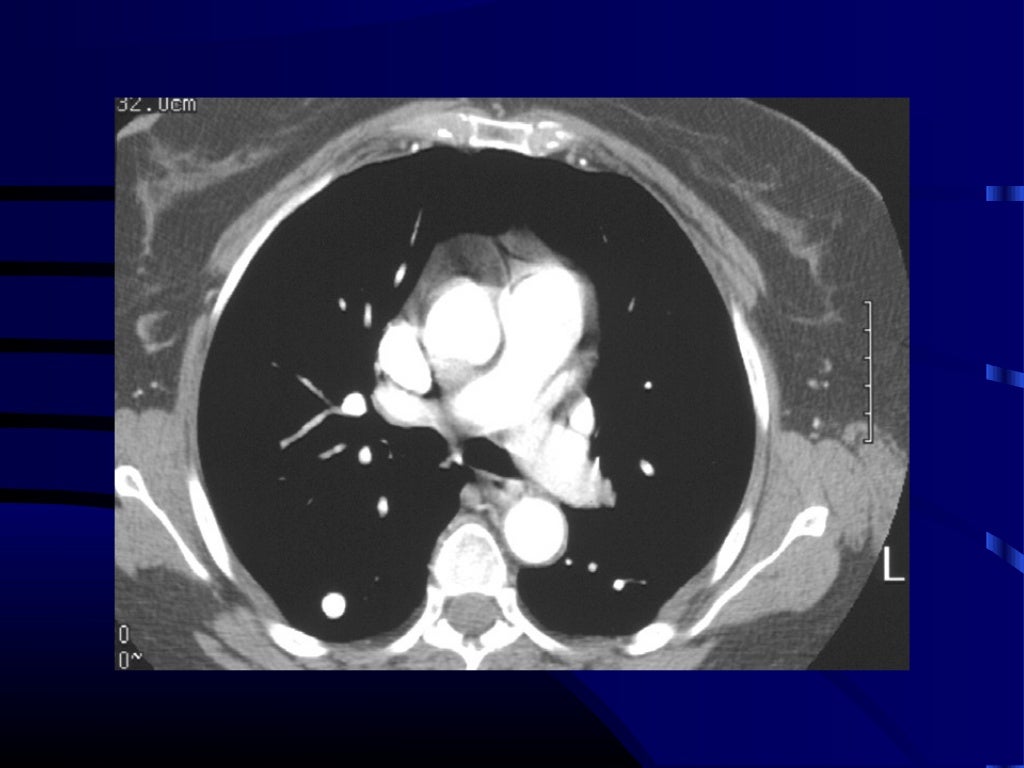

lung cancer staging cell non radiology 2009 version imaging scheme larger system

lung staging cancer 2009 cell non system larger version